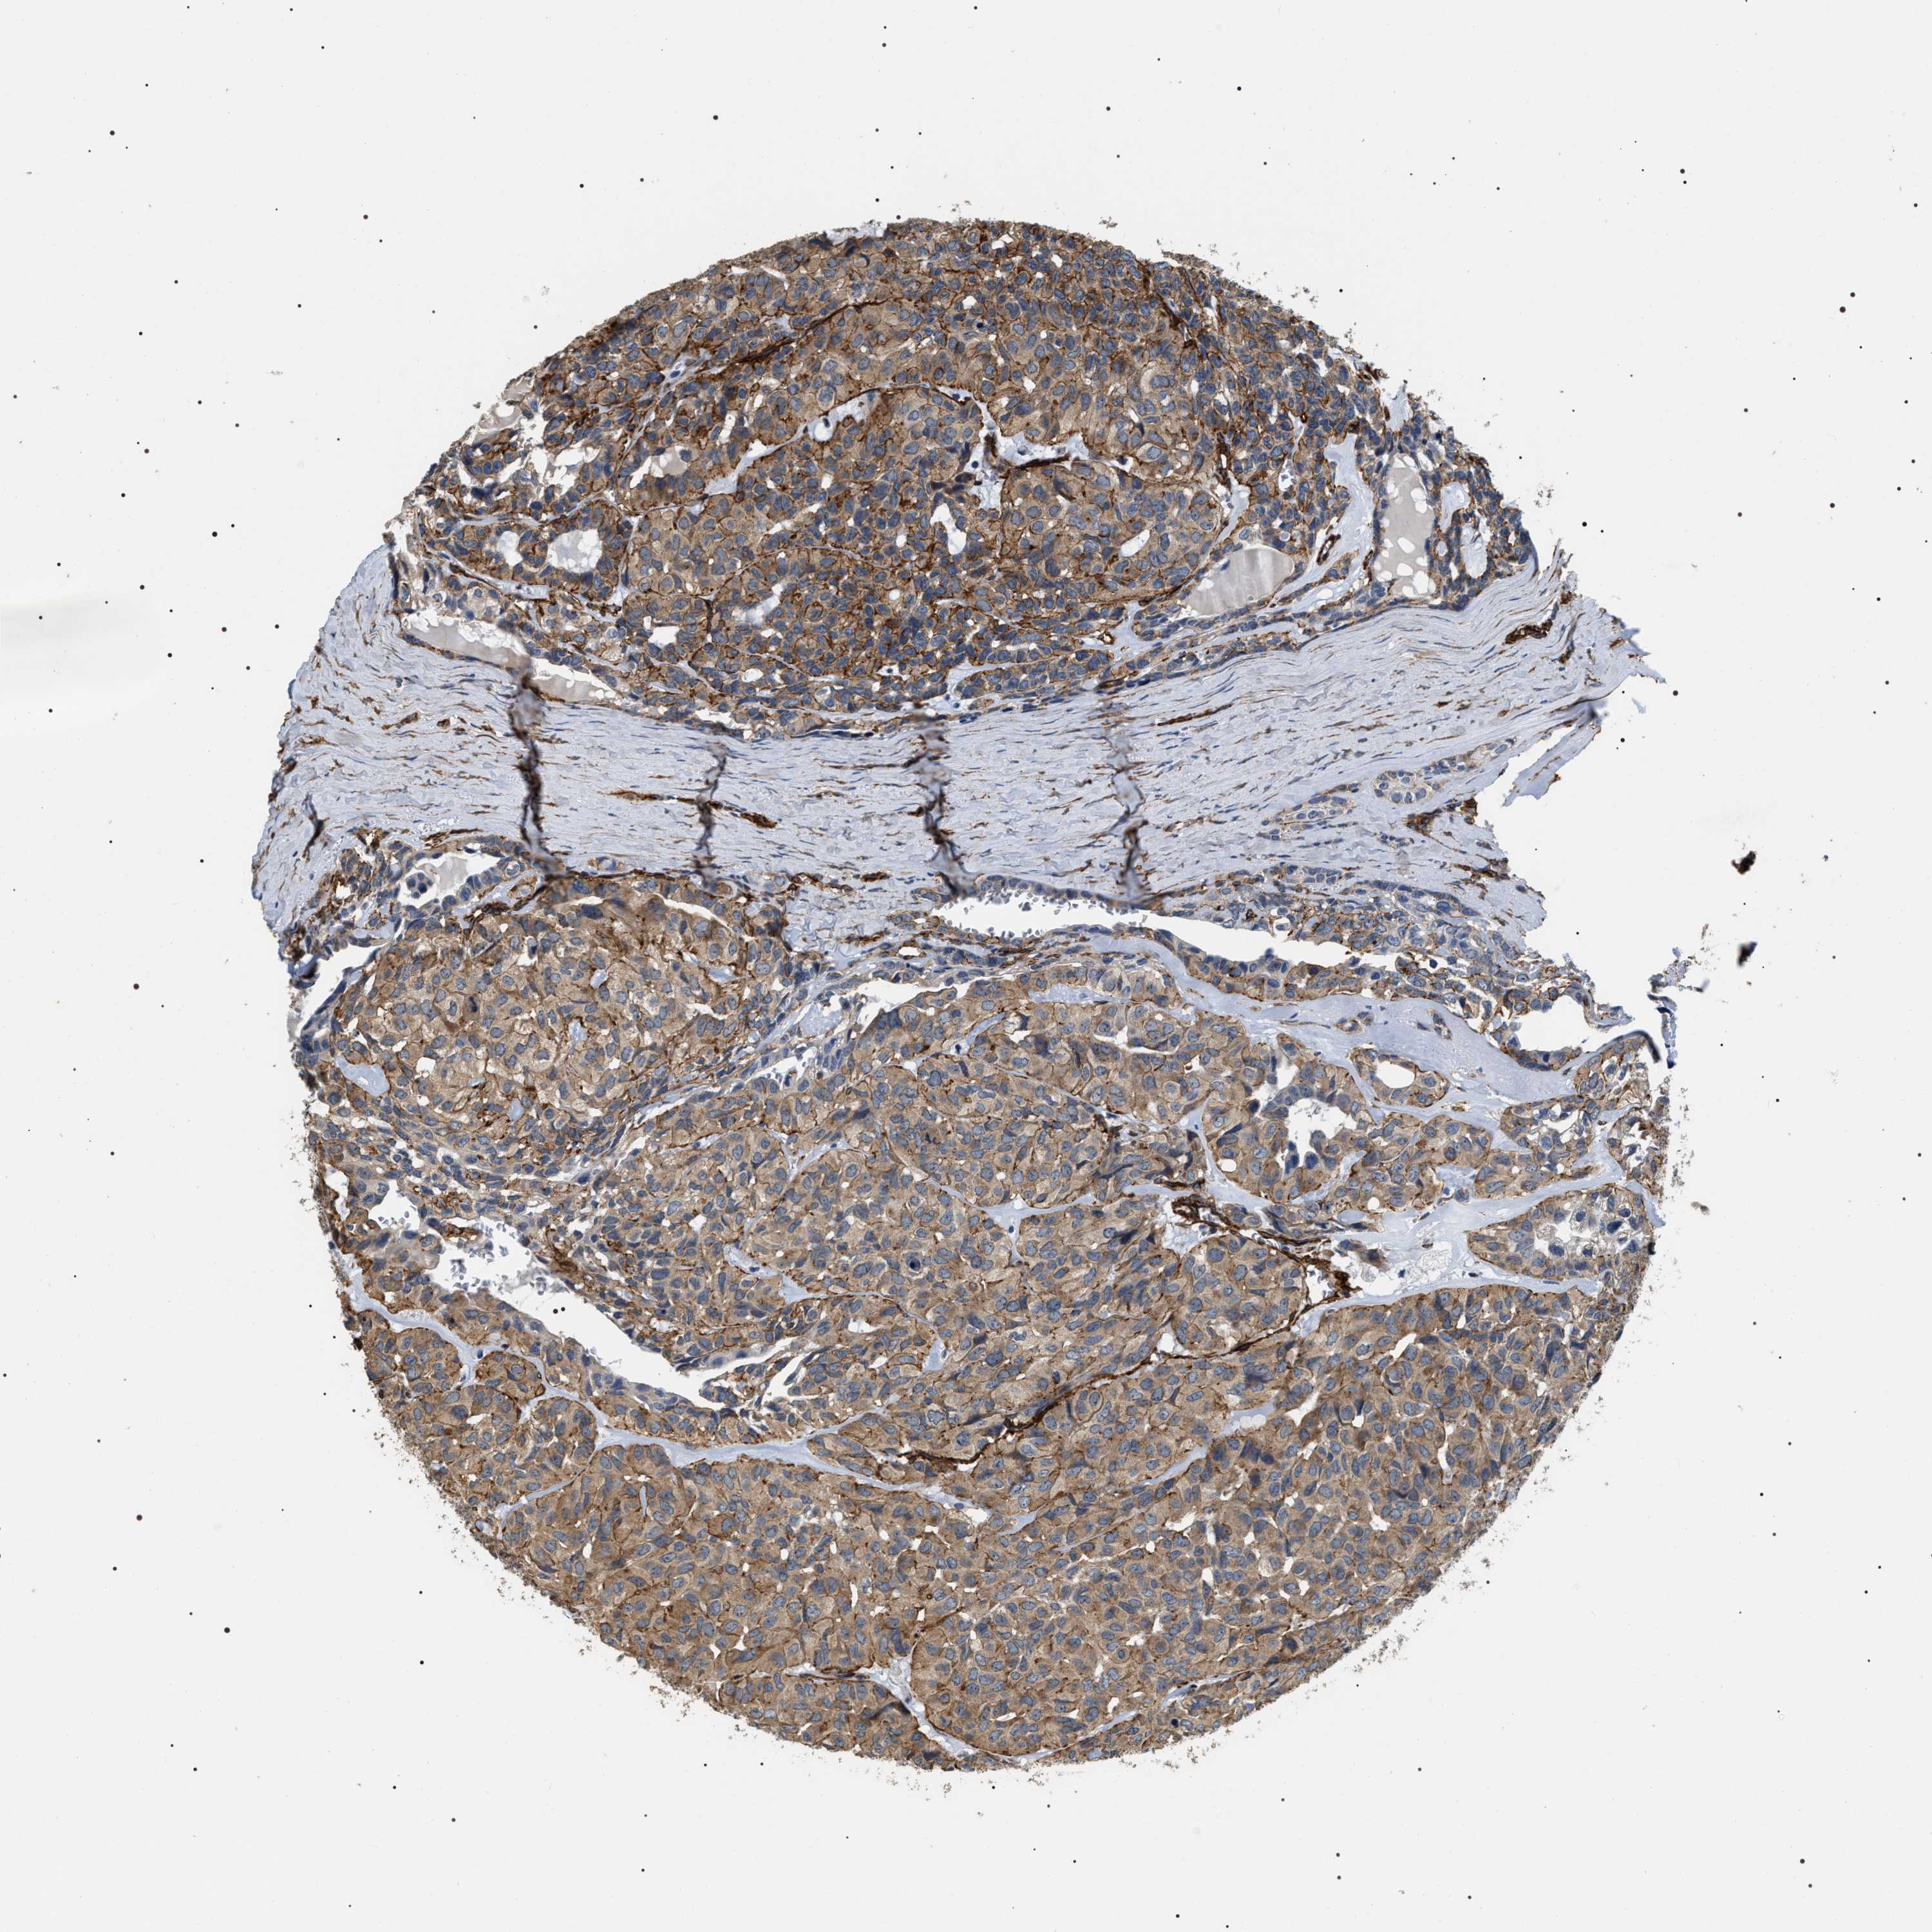

HEAD AND NECK CANCER - Protein expressioni

A mouse-over function shows sample information and annotation data. Click on an image to view it in a full screen mode. Samples can be filtered based on level of antibody staining by selecting one or several of the following categories: high, medium, low and not detected. The assay and annotation is described here.

Antibody stainingi

Antibody staining in the annotated cell types in the current human tissue is reported as not detected, low, medium, or high, based on conventional immunohistochemistry profiling in selected tissues. This score is based on the combination of the staining intensity and fraction of stained cells.

Each image is clickable and will lead to virtual microscopy that enables deeper exploration of all samples and also displays staining intensity scores, fraction scores and subcellular localization as well as patient and tissue information for each sample.

Antibody HPA020386

Staining

High

Medium

Low

Not detected

Intensity

Strong

Moderate

Weak

Negative

Quantity

>75%

75%-25%

<25%

None

Location

Nuclear

Cytoplasmic/membranous

Cytoplasmic/membranous,nuclear

Squamous cell carcinoma, NOS

Squamous cell carcinoma, metastatic, NOS

Adenocarcinoma, NOS